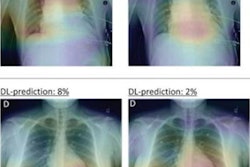

After x-ray acquisition, images were sent to the AI-CAD (Lunit INSIGHT CXR version 2.0.2.0) server and the AI-PACS (Infinitt Healthcare) server simultaneously, with the AI-PACS server randomizing patients 1:1 to one of the two groups; the experimental arm (AI-group; subject n = 5238, x-ray n = 5549) or the control arm (non-AI group; subject n = 5,238, x-ray n = 5,513).

One of three designated radiologists interpreted each x-ray using a structured reporting format integrated in AI-PACS and referring to the AI-CAD software results for subjects in the AI group.

Chest CT was obtained between the two groups within three months. Among those who underwent chest CT, the prevalence of significant nodules was similar and the performance of chest x-ray showed increased sensitivity in the AI group. Chest x-ray for these AI group patients also showed higher positive and negative predictive values, with very few false positives.

There was no difference in positive rates on x-rays and false referral rates. Twenty-four individuals were diagnosed with primary lung cancer (16 in the AI group and 8 in the non-AI group) and there was no significant difference in lung cancer detection rates.